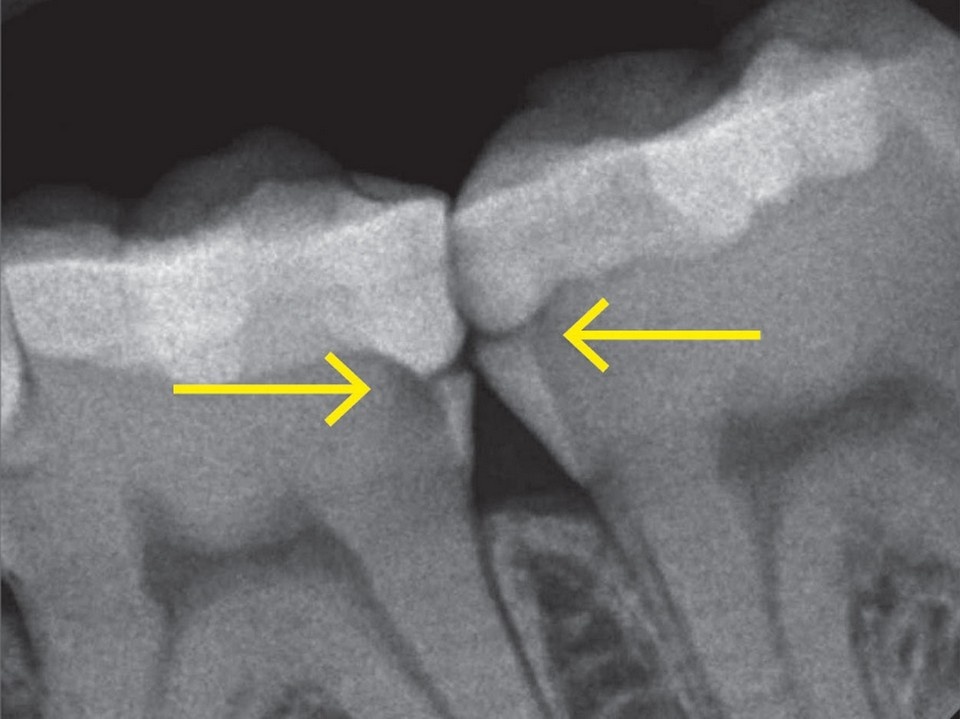

Как диагностируют?

• Рентген — показывает скрытые полости.